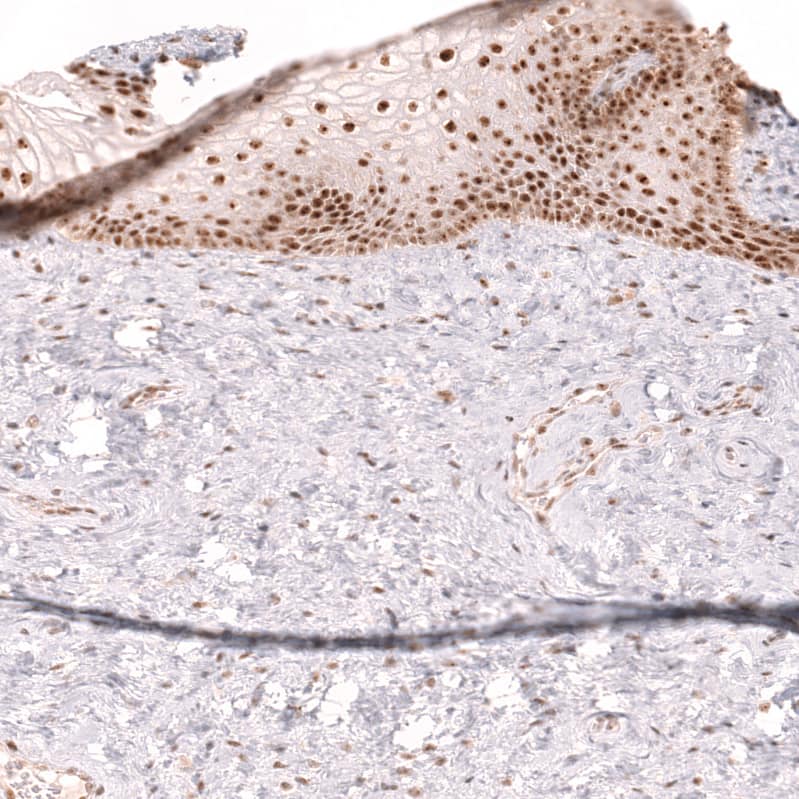

Staining of human cervix shows strong nuclear positivity in squamous epithelial cells.